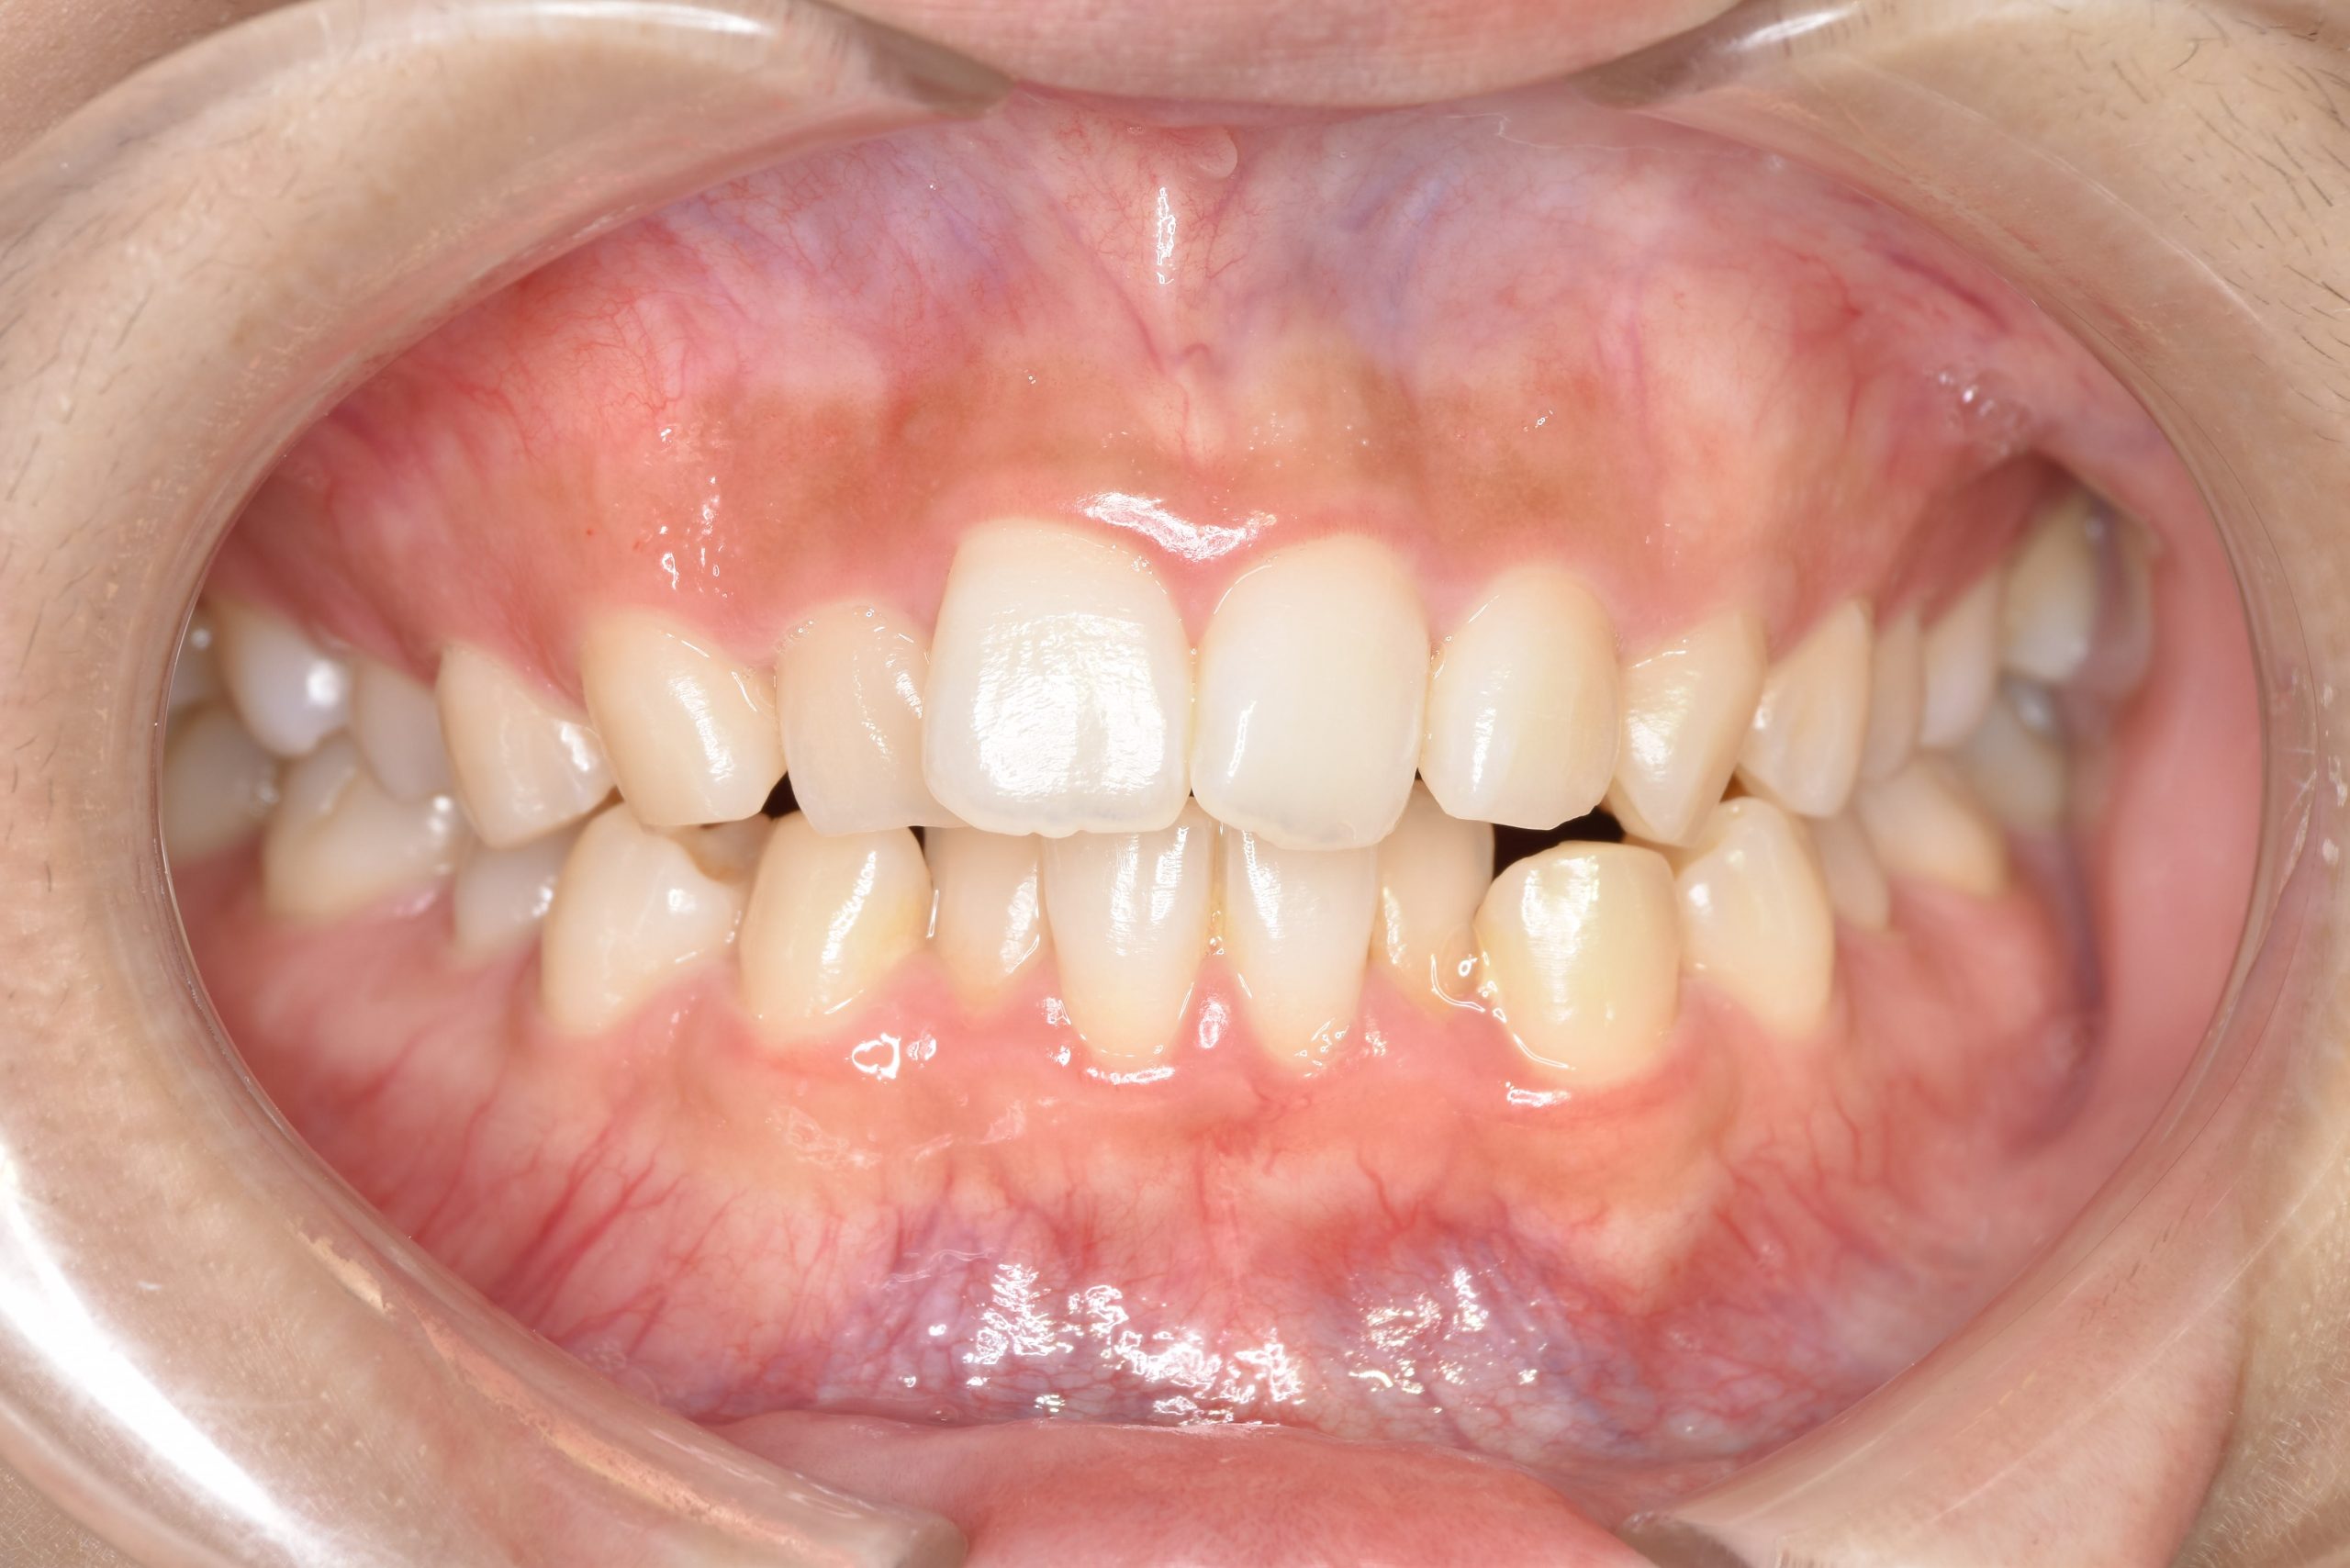

アフター

インビザライン矯正治療|症例_315

主訴 食べ物を前歯で噛み切れない|上顎の右側の歯が重なっている|下の歯がガタガタ

施術内容 MSEと下顎リンガルアーチを用いて上下顎骨を拡大した。

その後アライナー型矯正装置(インビザライン)を用いて非抜歯で歯牙を配列した。

口元の突出感、鼻閉症状、鼾は改善された。

治癒期間 1年6ヶ月間